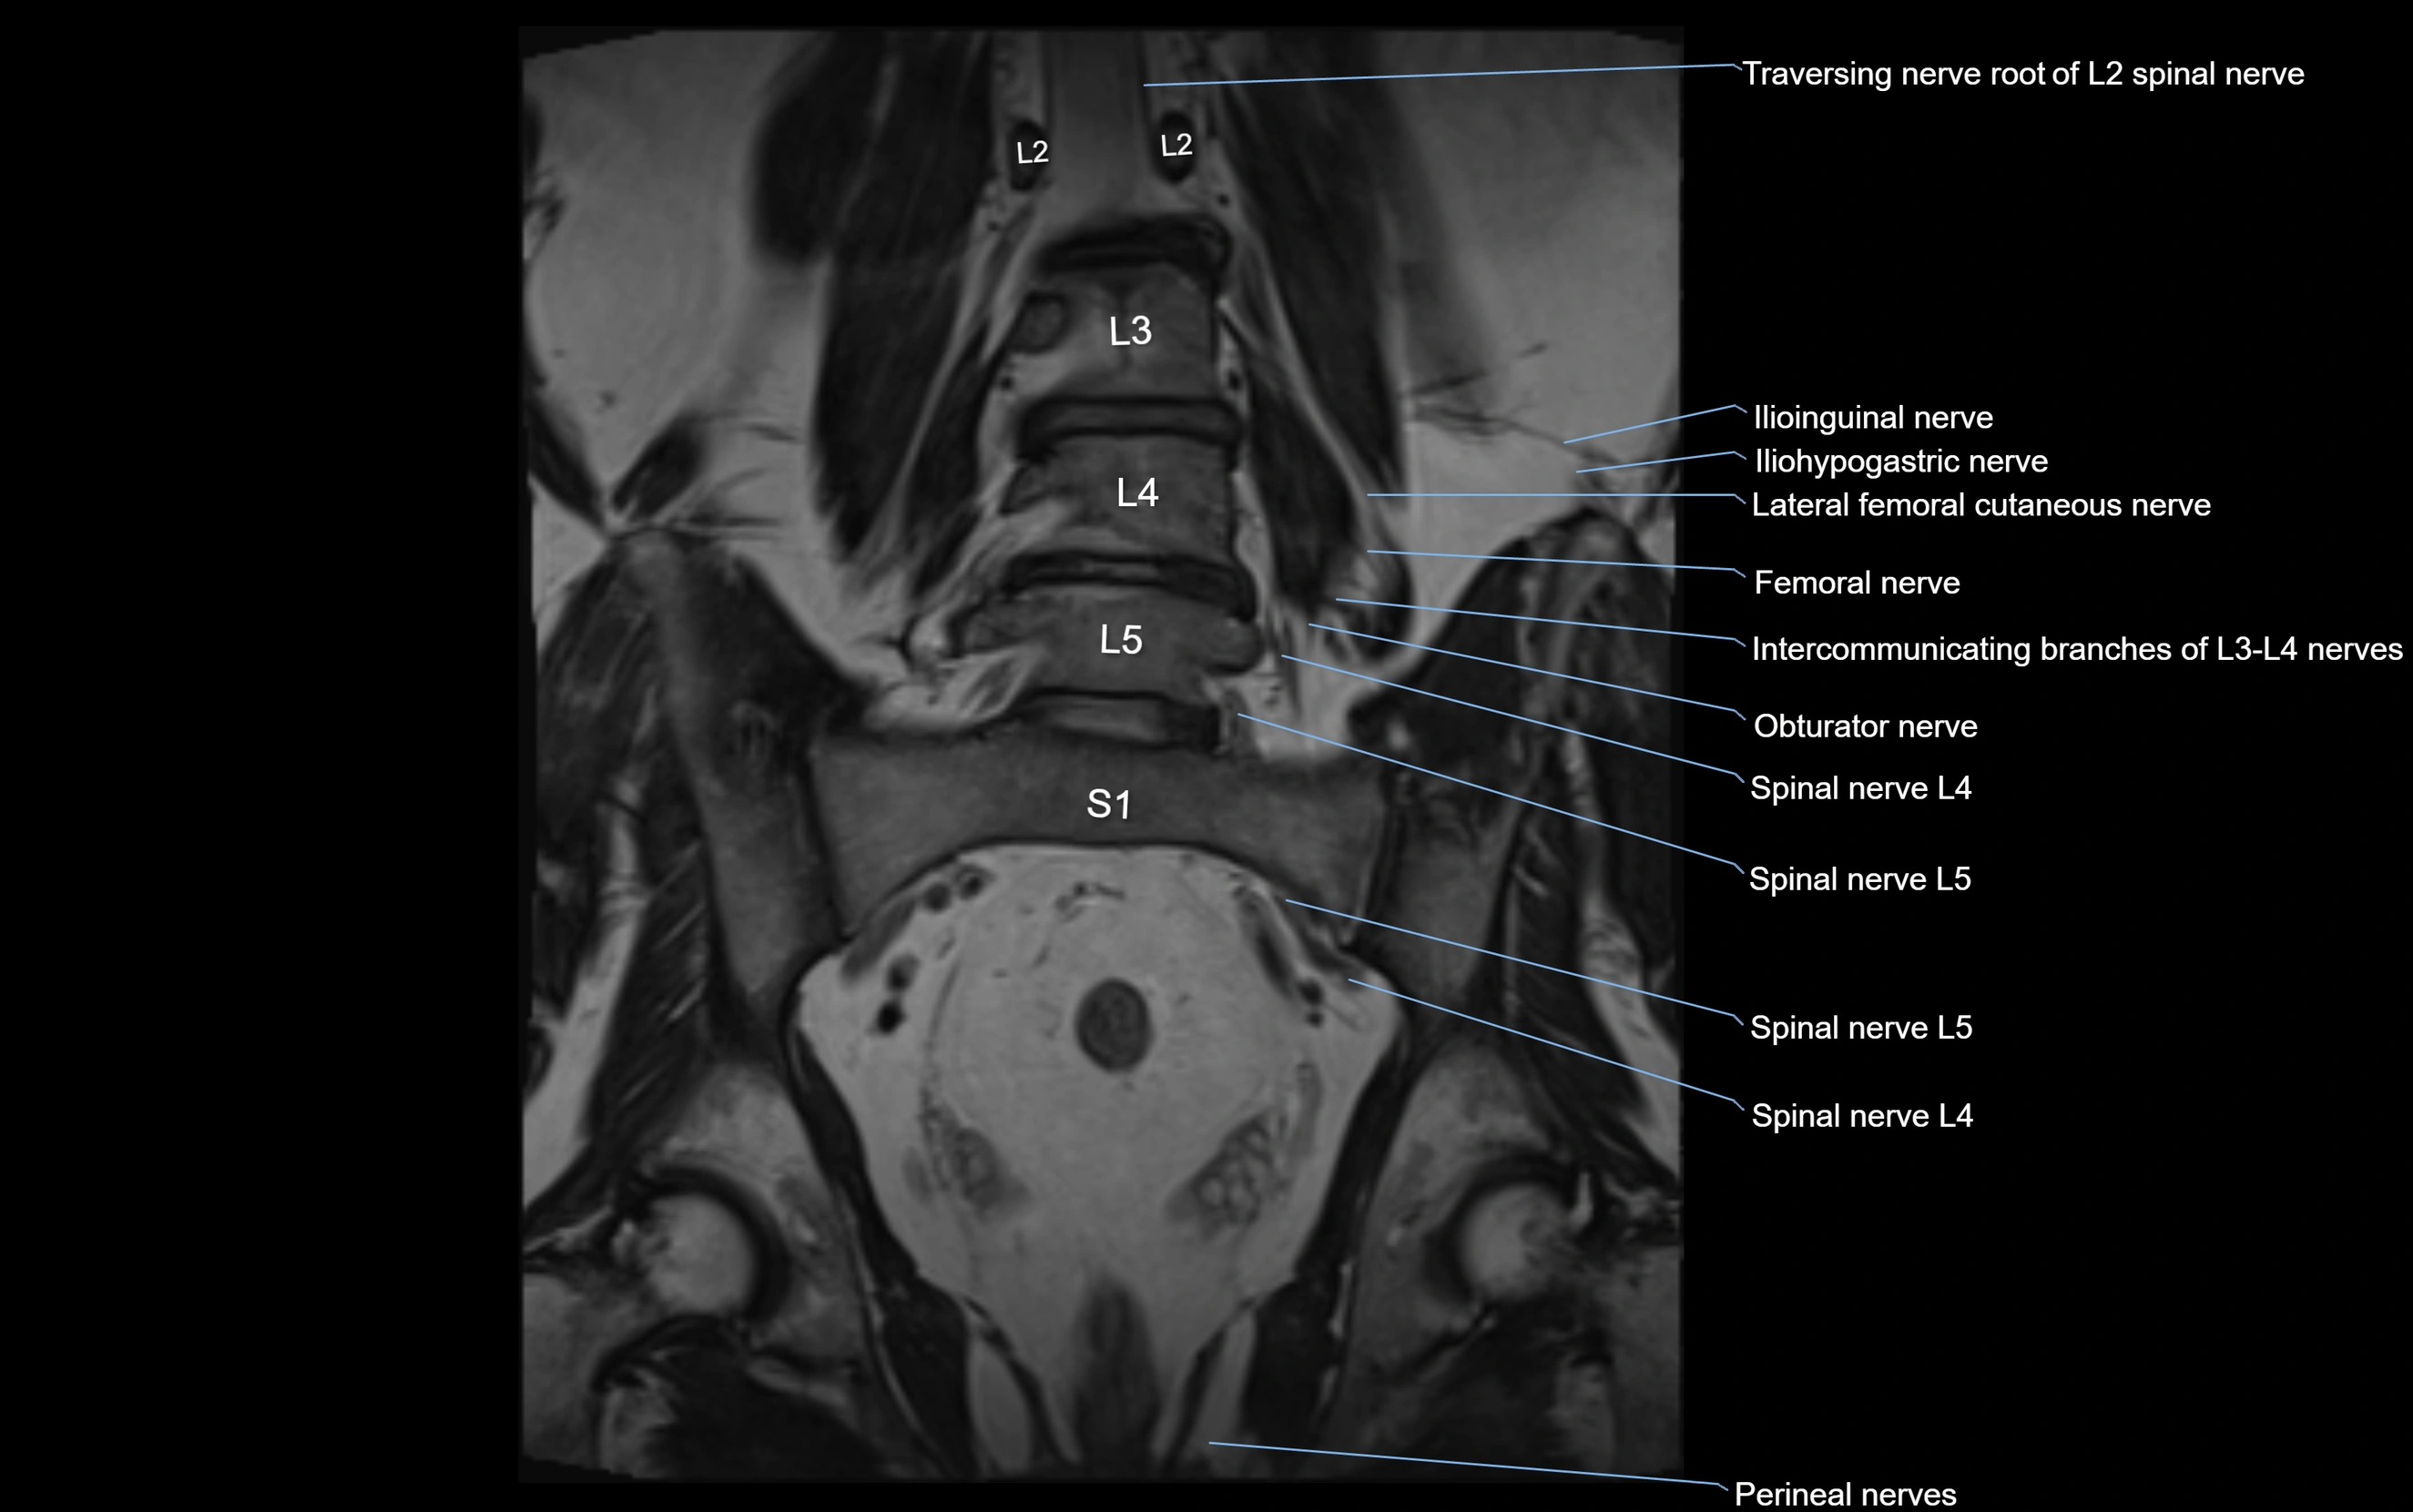

MRI image

image